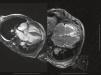

Late gadolinium enhancement (LGE) cardiac magnetic resonance imaging (MRI) is very useful in distinguishing between myocardial infarction, in which the enhancement is typically subendocardial, and myocarditis, in which it is subepicardial (Figure 1). In addition, various patterns have been described with different cardiomyopathies, in some cases enabling a specific diagnosis without invasive workup and risk stratification.1 Cardiac amyloidosis was previously thought to be present only when systemic amyloidosis was patently manifest. This has proved not to be the case, with cardiac MRI detecting increasing numbers of cases in patients with diastolic heart failure in whom cardiac involvement may be the first or sole manifestation. The pattern of LGE commonly found in cardiac amyloidosis is a global subendocardial enhancement with different contrast kinetics, the ventricular cavities showing no signal at all (Figures 2–6) compared to myocarditis and acute myocardial infarction, in which there is an intracavitary gray signal (Figure 1). Of 10 patients referred after echocardiography raised the suspicion of a cardiomyopathy, five were diagnosed with cardiac amyloidosis, two had images not suggestive of amyloidosis and were subsequently found to have Fabry's disease (Figure 7), and the other three probably had concentric left ventricular hypertrophy due to hypertension.